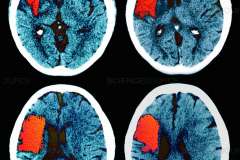

Stroke and dementia are two of the most common neurological disorders, and increasingly researchers are recognizing the link between the conditions.

Brain scan

Dementia is characterized by a loss of cognitive function, including problems remembering, reasoning and concentrating. Though an estimated third of people age 85 and older suffer from the condition, it is not an inevitable part of aging.

Stroke, which is the leading cause of serious long-term disability, occurs when blood supply to the brain is blocked or a blood vessel bursts. A stroke greatly increases a person’s risk of developing dementia.